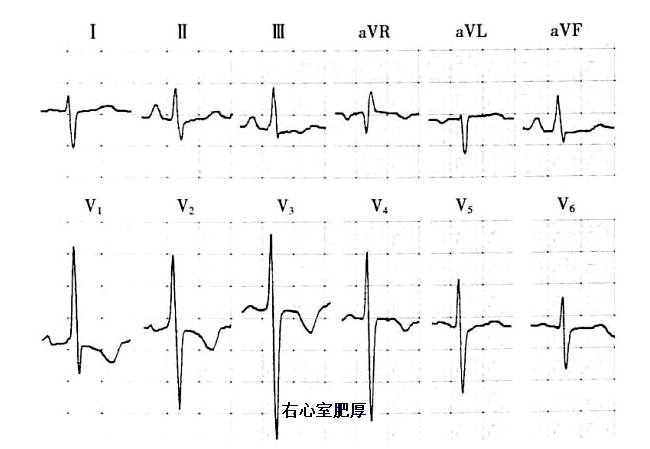

(1)当V1、V2出现高大R波时,表示存在右心室肥厚,当V5、V6出现高大R波时,表示左心室肥厚,具体如下图所示。当然单纯靠这点就判断心室肥厚有点欠妥当,临床还需结合心脏超声和心脏浊音界叩诊。

图12